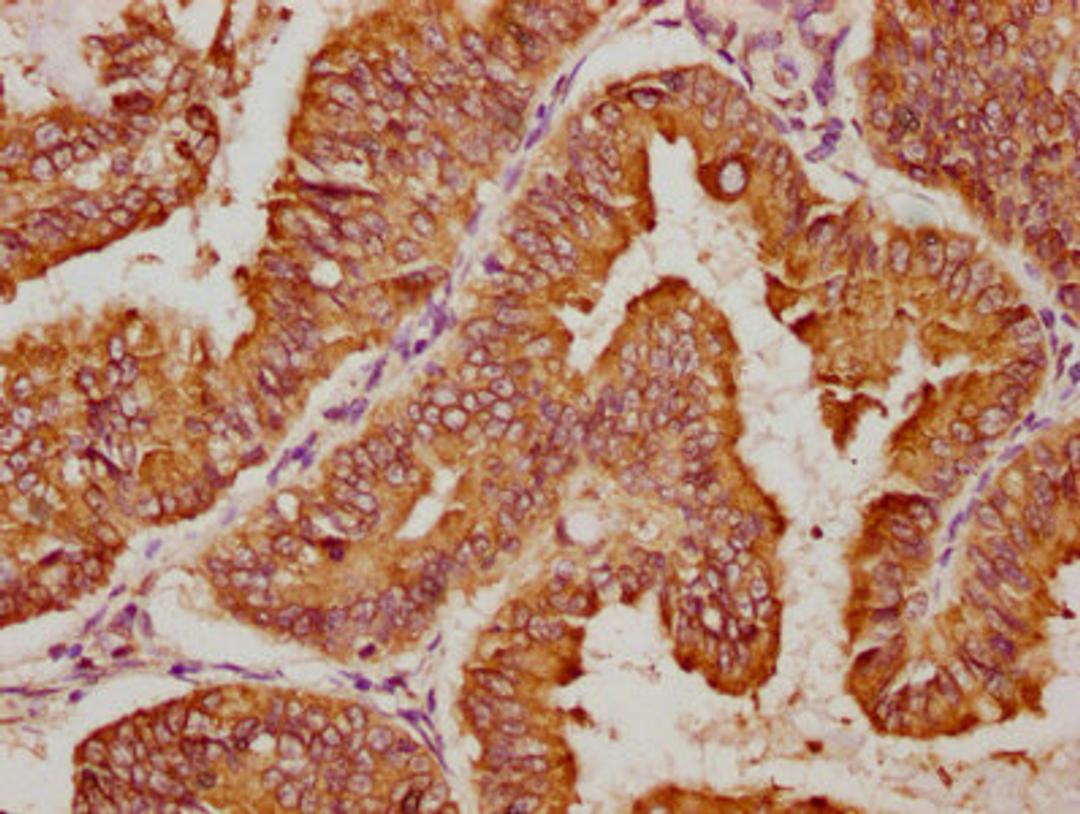

IHC image of CSB-PA809006LA01HU diluted at 1:100 and staining in paraffin-embedded human endometrial cancer performed on a Leica BondTM system. After dewaxing and hydration, antigen retrieval was mediated by high pressure in a citrate buffer (pH 6.0). Section was blocked with 10% normal goat serum 30min at RT. Then primary antibody (1% BSA) was incubated at 4°C overnight. The primary is detected by a biotinylated secondary antibody and visualized using an HRP conjugated SP system.